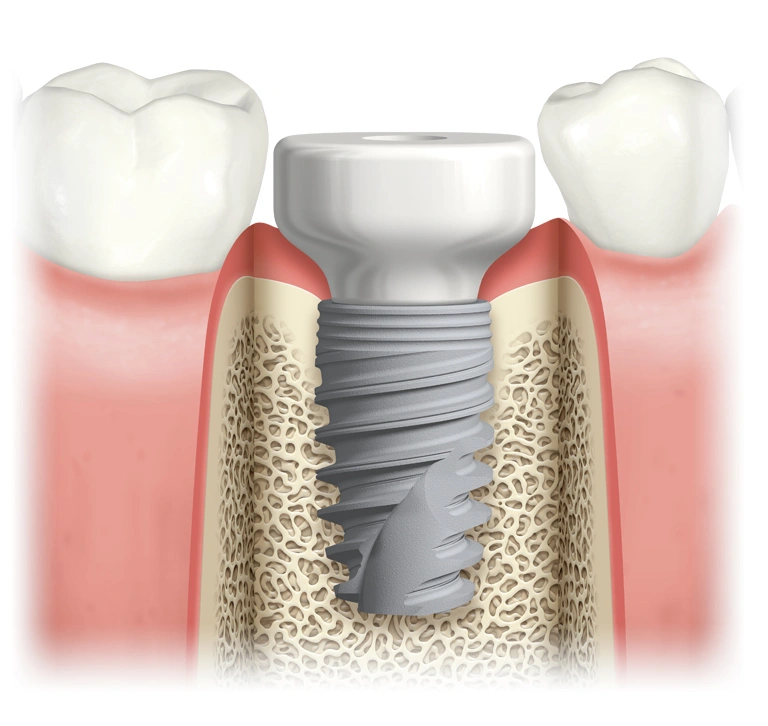

With conventional implants, also called single tooth implants (click here to learn more), you need 12 implants to support the crowns replacing your missing teeth. This means the cost of treatment is very high. Conventional or traditional dental implant treatments also increase the likelihood of requiring a dental bone graft before implants can be placed. With an All-on-4 or All-on-6 dental implant procedure we only require 4 or 6 dental implants to secure a full arch of teeth.